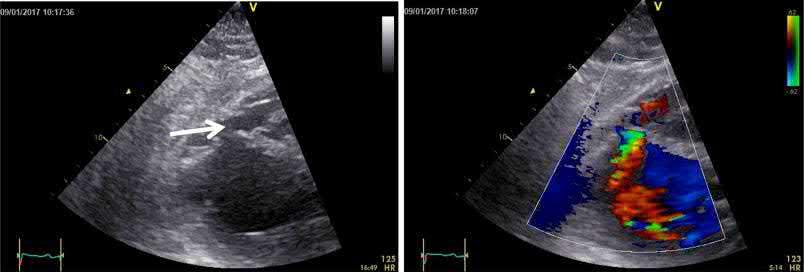

The era of modern non‐invasive cardiac imaging started with echocardiography, which is very convenient for out‐patient and bedside evaluation. Echocardiography plays an important role, especially in the acute phase, for evaluation of LV function and mechanical complications of acute MI (Figures 1.2, 11.2, and 11.3). The method is also of clear value in chronic IHD patients for the study of LV function; both global and regional wall motion abnormalities can easily be detected (Bogaty et al. 2002; Matetzky et al. 1999; Mitamura et al. 1981). Both the non‐ST‐elevation acute coronary syndrome (NSTE‐ACS) and ST‐elevation MI (STE‐ACS) guidelines highlight the importance of transthoracic echocardiography in the diagnosis, differential diagnosis and risk stratification in ACS patients (Roffi et al. 2016; Steg et al. 2012). Visualization of a regional decrease in systolic movement of the inner layers of the LV and a decrease in myocardial thickening are the main criteria for the diagnosis of myocardial ischemia (Figure 1.2) (Leischik et al. 2016). Yet, echocardiography cannot always differentiate between an old infarction and acute ischemia. Echocardiography may aid in decision‐making in the emergency room when the ECG findings are inconclusive, since regional wall‐motion abnormalities occur within minutes following coronary occlusion, well before necrosis. However, lack of regional wall motion abnormalities cannot rule out acute ischemia, especially in patients with left ventricular hypertrophy (Neuman et al. 2004). Growing evidence of the use of tissue Doppler and strain imaging in acute myocardial ischemia is

Figure 1.2 ECG‐echocardiography correlation. Post‐reperfusion ECG of an 82‐year‐old patient with LAD occlusion. The ECG shows anteroapical STE‐ACS. There is ST‐segment elevation in I and aVL: although the occlusion was in the mid‐LAD, there was one or more diagonal branches distal to the occlusion (Eskola et al. 2007) End‐diastolic (left) and end‐systolic (right) apical long‐axis views show hypokinesia of the apex and compensatory hyperkinesia of the basal septum and lateral wall. Strain rate imaging (bull’s eye) clearly delineates the region with apical dyskinesia (see Plate 2 in color plates).

The persistence of ST elevations and hemodynamic instability should raise the suspicion of a post‐infarction mechanical complication. The echocardiogram should be repeated in several projections. Next figure shows a rupture of the interventricular septum (arrow) that had gone unnoticed. In this case the ECG pattern was an important key to raise the suspicion of an important complication of the disease.

A 60‐year old woman with epigastric discomfort. Her medical history included a treadmill exercise test several years earlier because of negative T waves in V2 to V4 found on a routine

ECG (Figure). The ECG findings were considered a normal variant in a woman and the treadmill test was negative. The ECG shows sinus rhythm with mild biphasic T waves in V2 to V4.

Case 2

An echocardiogram was performed (left diastole, right systole)

Suggestions for diagnosis:

1) Congenital apical aneur ysm

2) Apical aneur ysm secondary to undiagnosed silent infarction

3) Apical congenital diverticulum

4) Apical hypertrophic cardiomyopathy

Correct answer: 1

The echocardiogram (of intermediate quality) detected an apical aneurysm. The ventricular aneurysm with a paradoxical expansion during systole and end‐systolic flow pattern from the ventricle to the aneurysm was better demonstrated with CMR (next figure, arrows) (Fiol M, et al. Int J Cardiovasc Imaging. 2015;31: 1261–1262). A “normal variant” is uncommon, but still possible, at the age of 60.